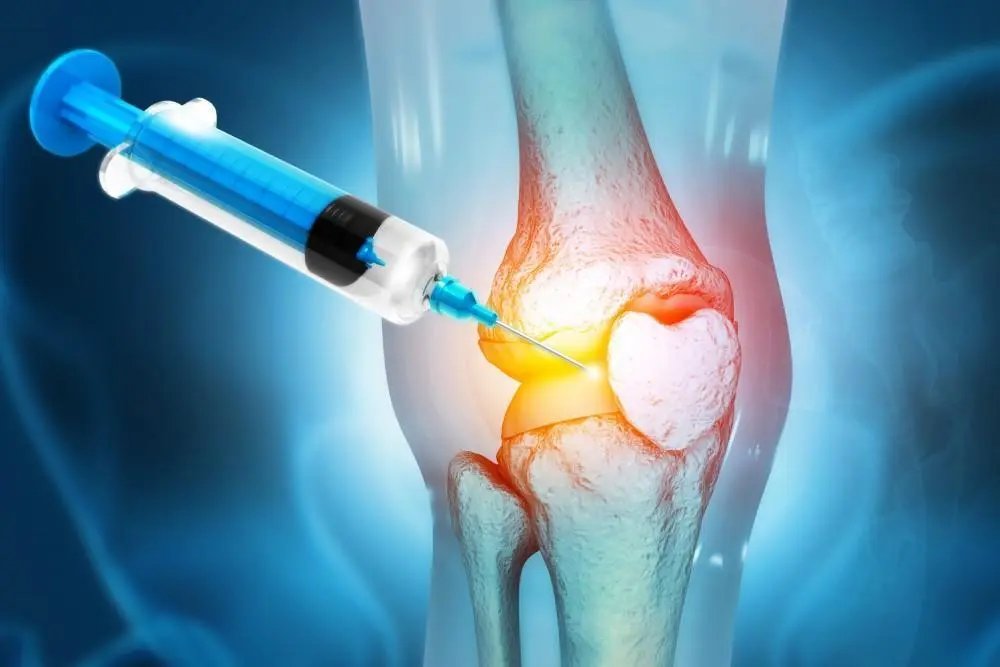

How Does PRP Therapy Work?

The blood of a patient is used to heal the body; that’s why PRP therapy is fun. Its principle of operation is basically:

- Collect Blood Samples: The first procedure is pretty basic; it involves drawing blood. It’s just like having blood drawn for a regular blood test.

- Centrifuge Process: The blood sample is put inside the centrifuge. This powerful gadget spins the blood towards the wall at extremely high speeds to separate it into its components.

- Plate-Rich Plasma: And this separates PRP from the plasma. The PRP, which stands for platelet-rich plasma, is composed of small cells that have an awesome job in healing.

- Injection: Use of an imaging technique to guide the direct injection of PRP into the knee joint.

- Healing: After injecting the platelets, they start doing their work and issuing growth factors, which stimulate the repair and regeneration of damaged body tissues, making PRP for joint pain last and effective in decreasing inflammation and promoting pain resolution.